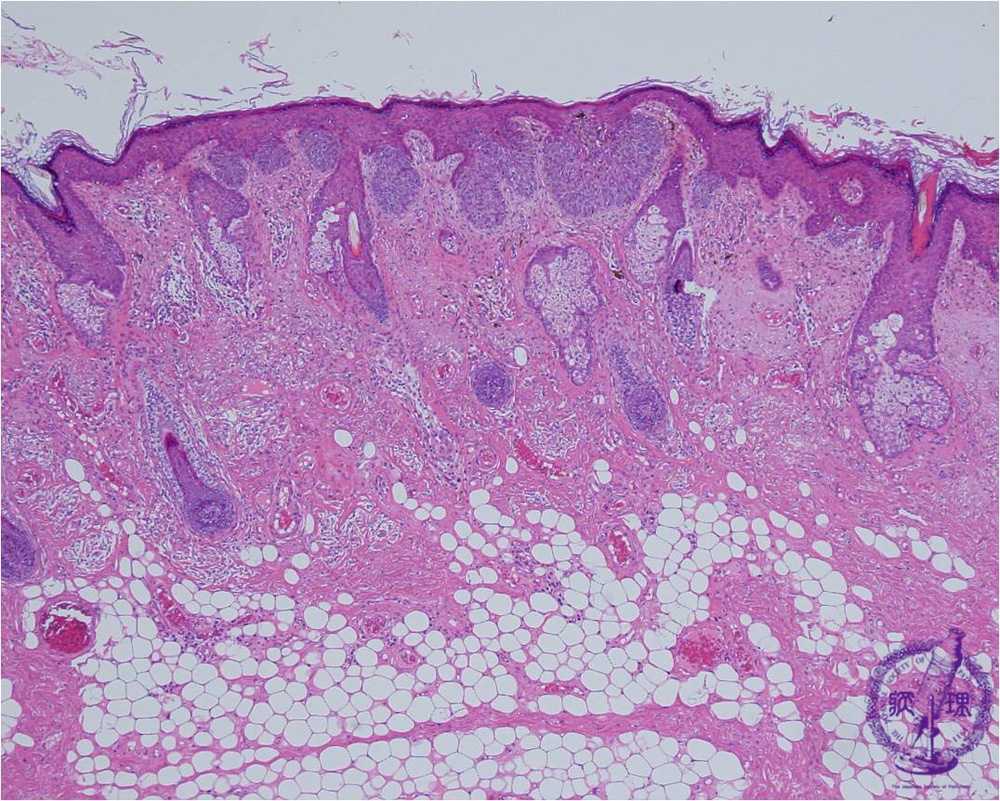

- ★(7)Basal cell carcinoma

Microscopic findings: Basal cell carcinoma is composed of cell types that have their origin in the fetal hair germ (trichoblast) and the cells in these tumors retain a resemblance to their cell of origin. . It is the most frequent skin malignancy, typically occurs on the sun-exposed areas. It is a locally invasive tumor and complete excision is curative. Metastatic progression is rare and if complete excision is achieved the tumor has a very good cure rate.